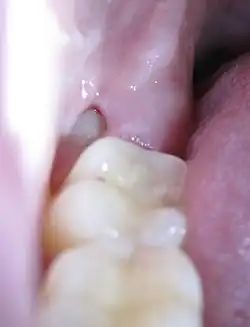

Dentitio difficilis im bleibenden Gebiss

Zahn 38: Verlagerter Weisheitszahn mit „Schmutzwinkel“ zwischen den Zähnen.

Ursache

Die Dentitio difficilis tritt als Dentitionsstörung im bleibenden Gebiss fast ausschließlich beim Durchbruch von Weisheitszähnen auf, vorwiegend im Unterkiefer. Die Ursache liegt im Platzmangel für diese (zuletzt durchbrechenden) Zähne. Der Platzmangel entstand in der menschlichen Evolution durch eine bei zahlreichen Menschen entstandene Verkürzung des Unterkieferkörpers. Im Unterkiefer kommt hinzu, dass durch den aufsteigenden Ast des Unterkiefers (Ramus mandibulae) an der distalen Fläche der Zahnkrone oft eine Zahnfleischtasche entsteht, die der Zahnreinigung nicht hinreichend zugänglich ist. In dieser künstlichen Zahnfleischtasche können sich Bakterien und Speisereste ansammeln, die zu einer eitrigen Entzündung führen. Besonders bei einem verlagerten oder teilretinierten Zahn ist diese Gefahr gegeben, wobei dann auch andere Zahnflächen als „Schmutzwinkel“ in Frage kommen. (Siehe nebenstehende Abbildung)